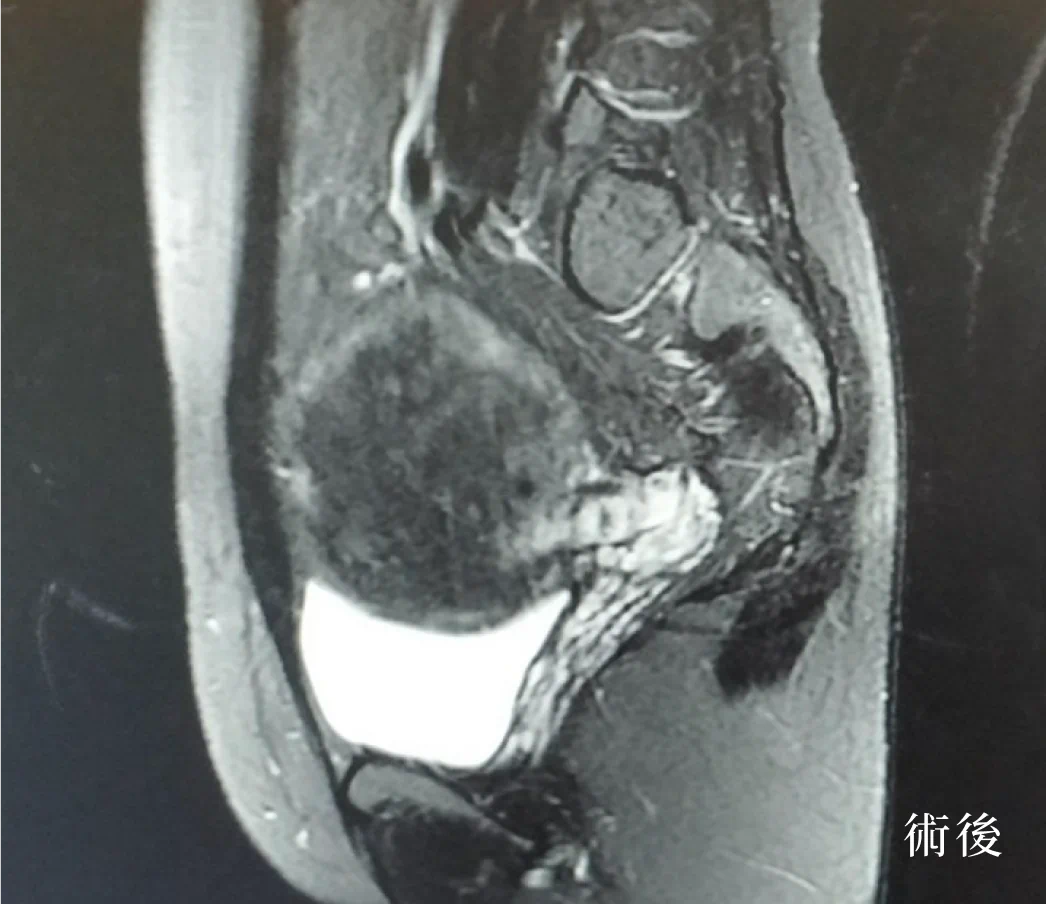

個案在海扶刀治療前,子宮肌瘤最大的約9*8 cm,經由吳昆哲醫師用海扶超音波聚焦消融術後,不僅表皮無傷口,做完手術的隔天即可出院,恢復正常的日常生活及輕鬆的返回職場工作。

生安海扶中心也有專人安排做術後的MRI追蹤,輔導健康生活模式及專線諮詢和子宮保健操,以及持續關心個案在術後身心的狀況,讓個案在術後得到安心又完整的照顧。